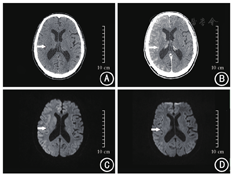

入院体检:体温36.2 ℃,心率68次/min,呼吸22次/min,血压129/65 mmHg(1 mmHg=0.133 kPa)。神志清楚,言语流利;双侧瞳孔等大等圆,对光反射灵敏;双肺呼吸音清,未闻及干湿性啰音;心律齐;腹平软,无压痛、反跳痛及肌紧张;四肢肌力、肌张力正常;双侧指鼻试验及跟膝胫试验稳准,双侧巴氏征阴性,闭目难立征阴性。实验室检查:血、尿、便常规,凝血功能,肝、肾功能,心肌酶,甲状腺功能等均未见异常,同型半胱氨酸21.8 μmol/L(参考值:4.0~15.4 μmol/L)。头部CT示右侧大脑皮层未见明显异常(图1A)。入院诊断:右侧颈总动脉与颈内动脉起始处重度狭窄。入院当日予阿司匹林肠溶片100 mg口服、1次/d,硫酸氯吡格雷75 mg口服、1次/d,阿托伐他汀钙20 mg口服、1次/d,吡拉西坦氯化钠注射液250 ml静脉滴注、2次/d。入院第3天(6月14日)13:00,患者在局麻下接受主动脉弓造影+全脑动脉造影+右侧颈内动脉支架置入术,对比剂为碘克沙醇;13:30,采用高压泵经右股动脉分10次注入未加温的碘克沙醇注射液共150 ml,15:30手术结束。患者术后意识清楚,神经系统查体无阳性体征。术毕查头部CT:右侧大脑皮层密度增高、脑沟内见高密度影(图1B),考虑对比剂滞留。术后10 h(6月15日1:45),患者出现发热,体温38.4 ℃,给予注射用萘普生钠275 mg静脉滴注退热治疗,体温未见明显下降,此后患者出现嗜睡,同时出现意识障碍、失语、饮水呛咳。急查体:不完全运动性失语,双侧咽反射迟钝,伸舌明显左偏,左侧肢体上下肢肌力Ⅱ级,肌张力减低,左侧巴氏征阳性,右侧肢体活动自如,右侧巴氏征阴性。美国国立卫生研究院卒中量表评分为13分(意识水平:1分,意识水平提问:2分,面瘫:2分,上肢运动:3分,下肢运动:3分,言语障碍:2分)。查头部磁共振成像(magnetic resonance imaging,MRI)示右侧大脑皮层信号增高,脑沟变浅(图1C)。考虑为对比剂脑病(contrast-induced encephalopathy,CIE)。立即给予充分水化,注射用甲泼尼龙琥珀酸钠80 mg静脉滴注、1次/d,甘露醇注射液125 ml静脉滴注、2次/d,左乙拉西坦0.25 mg口服、2次/d治疗。术后第2天(6月16日),患者体温恢复正常,言语不利情况好转,可简单表达,左侧肢体无力症状减轻;当日17:34,患者出现癫痫发作性抽搐1次,发作时双眼向左侧凝视,牙关紧闭,双上肢抖动,双下肢紧绷,持续约3 min后自行缓解;立即予丙戊酸钠0.2 g口服、2次/d对症治疗;术后第3天(6月17日),患者意识清楚,言语流利,左侧肢体无力较前好转,可自行活动,无饮水呛咳,无发热及抽搐;术后第5天(6月19日),患者症状完全缓解。复查头部MRI示右侧大脑皮层高信号降低,脑沟恢复正常(图1D)。患者住院治疗10 d后上述症状完全缓解,病情好转出院。出院后1、3、6个月回访,患者无不适主诉。

本例患者既往无脑卒中和神经系统疾病等病史,入院时神志清楚,神经系统检查无阳性体征;行主动脉弓造影+全脑动脉造影+右侧颈内动脉支架置入术前头部CT示右侧大脑皮层未见明显异常;术后10 h出现发热、言语不利、肌张力下降、抽搐等症状,头部MRI示右侧大脑皮层信号增高,脑沟变浅。考虑为对比剂所致CIE。给予糖皮质激素、甘露醇脱水治疗3 d后神经系统症状好转。采用Naranjo不良反应评分标准[1]对患者CIE与碘克沙醇关系进行评分的结果为8分,说明患者的CIE很可能为碘克沙醇所致。